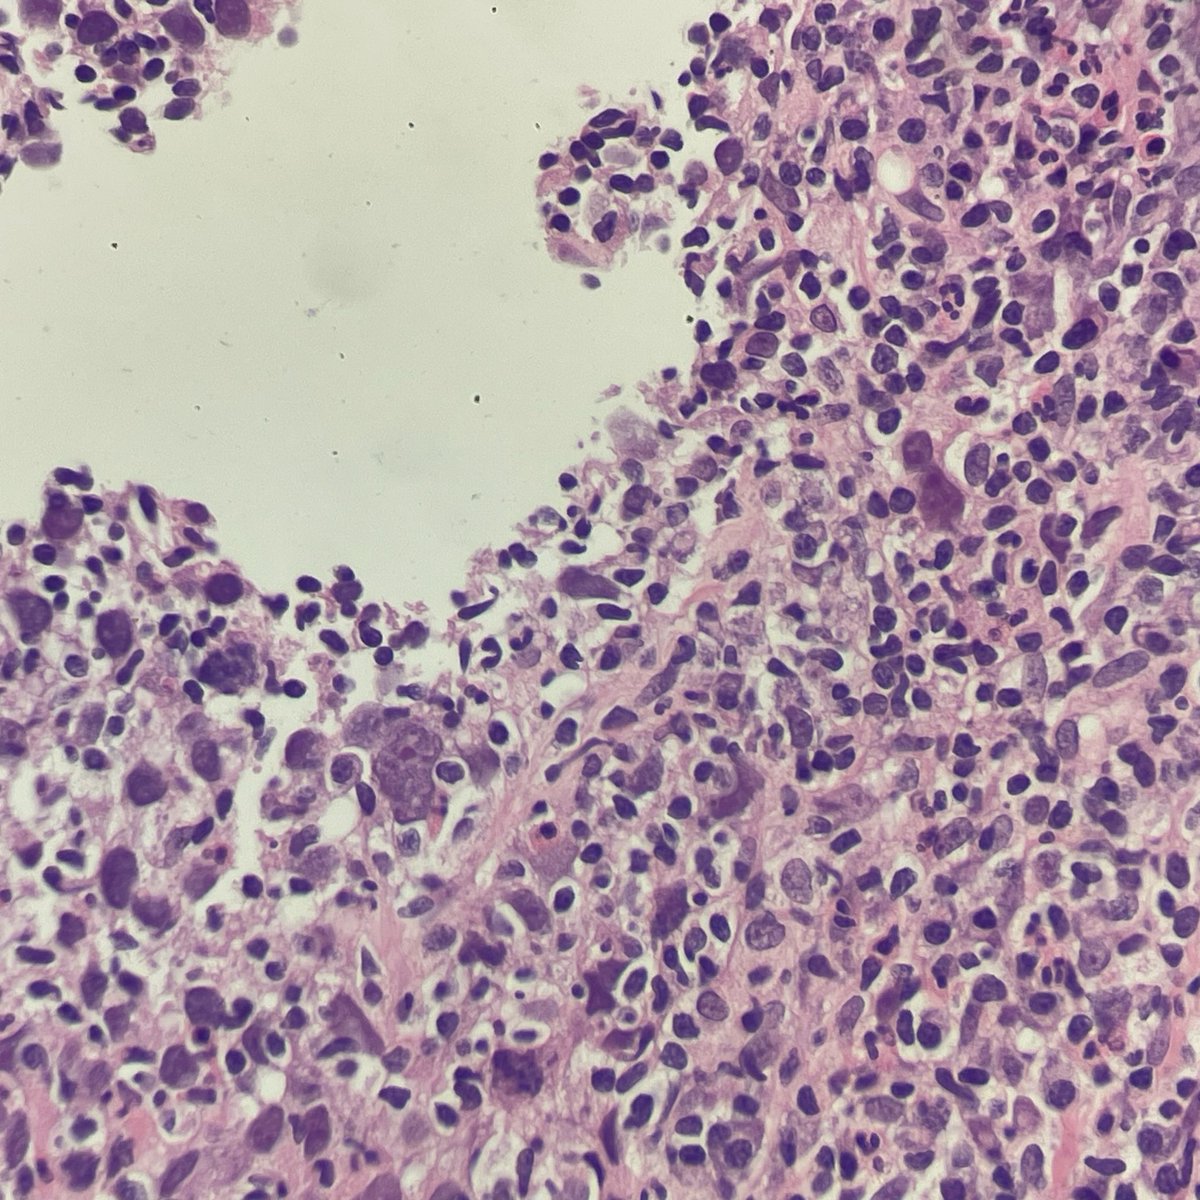

DLBCL, NOS showing signet ring cell-like morphology. #hemepath #PathTwitter